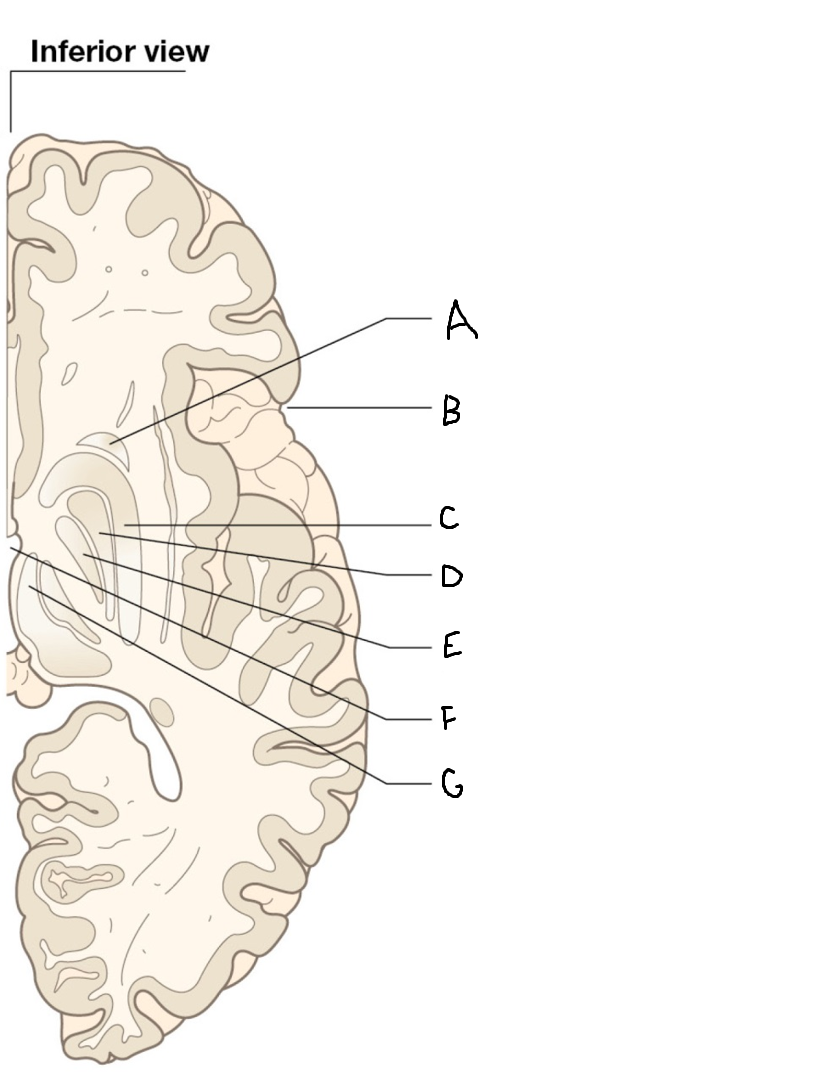

tail of caudate nucleus

A

head of caudate nucleus

C

putamen

D

external segment of globus pallidus

E

internal segment of globus pallidus

F

third ventricle

G

thalamus